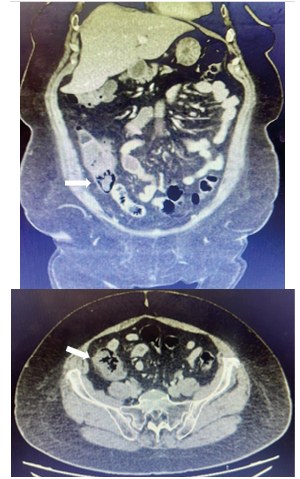

Se realizó una tomografía computarizada con contraste, la cual reveló la presencia de engrosamiento mural concéntrico del ciego asociado a neumatosis de la pared del mismo y signos de hipoperfusión local, sugerentes inicialmente de neoplasia colónica complicada. (Figura 1).

Figura 1. TAC en corte axial y coronal. Las flechas señalan engrosamiento concéntrico y neumatosis en ciego.